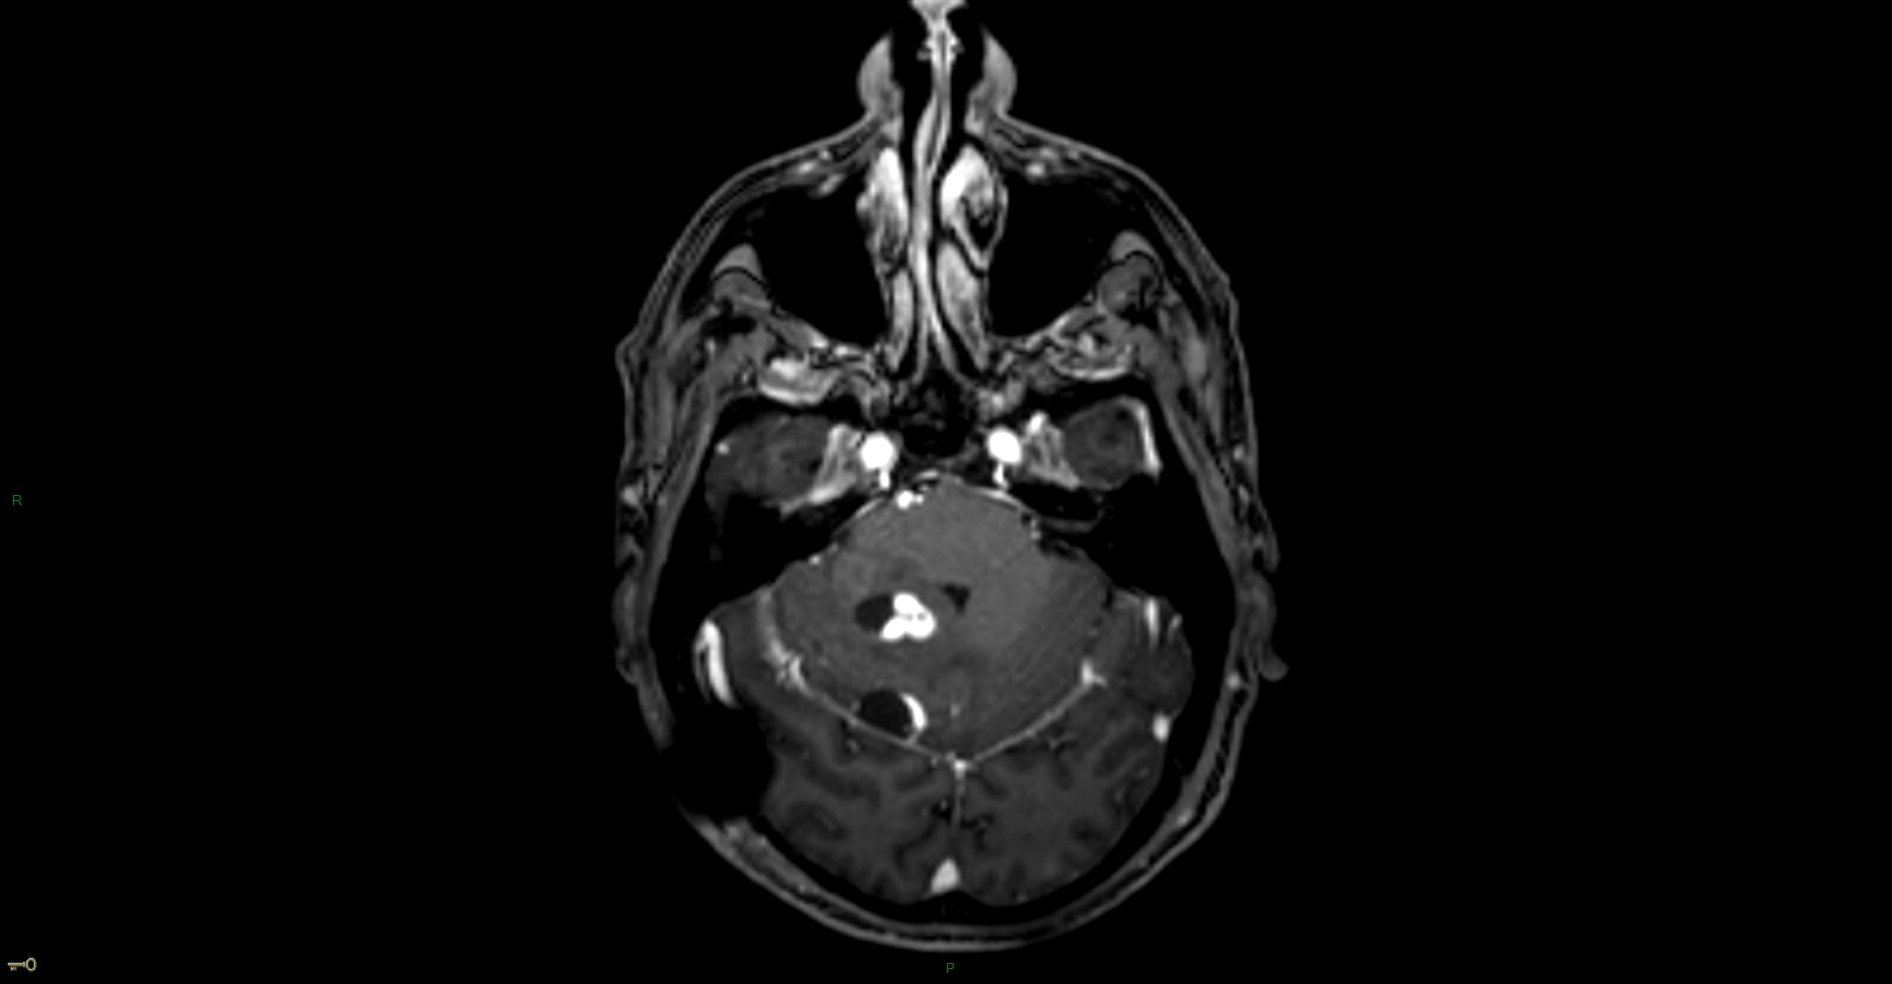

Hémangioblastome dans le cadre d'une maladie de Von Hippel Lindau